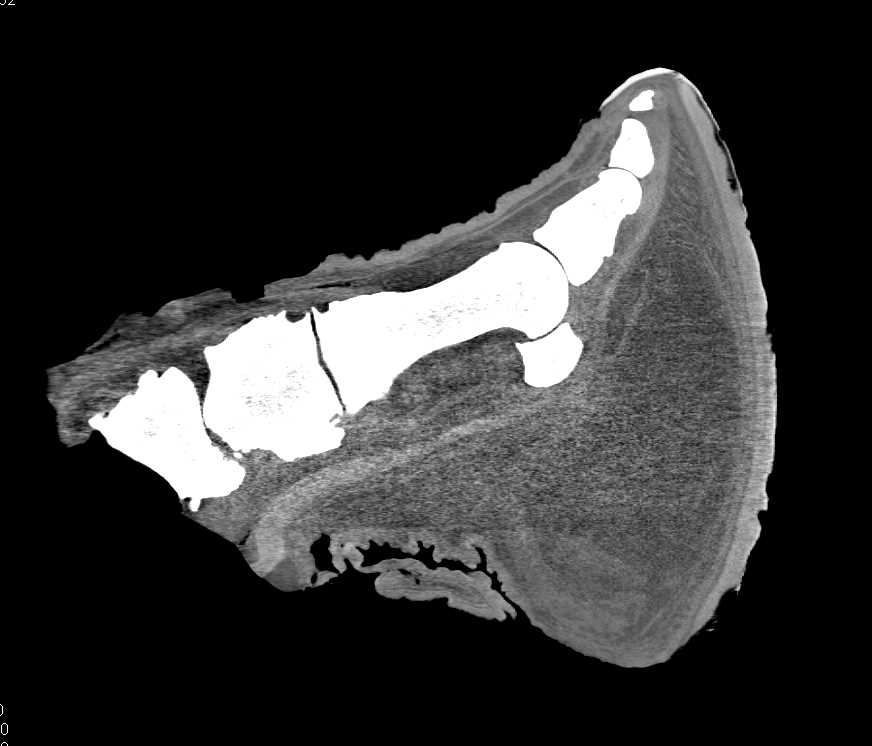

Intubated Bird in 3D